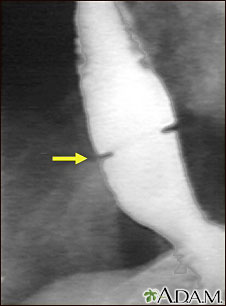

Lower esophageal ring

A lower esophageal ring is an abnormal ring of tissue that forms where the esophagus (the tube from the mouth to the stomach) and stomach meet.

A lower esophageal ring is a narrowing of the esophagus that occurs in a small number of people. The cause of the problem is unclear, but many believe that it is caused by acid reflux.